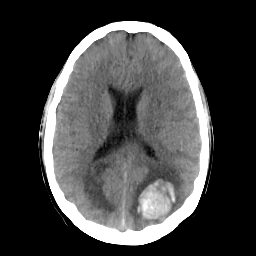

In this study, the dataset introduced in [8], which is publicly available111https://github.com/ChengBinJin/MRI-to-CT-DCNN-TensorFlow, is used for performance evaluation. It consists of 367 paired CT and MR images with the size of 512256. In the original dataset, it is noted that several CT images have stereotactic head frame that was used in Gamma Knife treatment. This head frame manually removed from the CT images. In addition, there exist various CT and MR slices that brings incredible difficulty in training the generator. Therefore, 100 images are selected from similar slices for each modality, in which 90 and 10 images are used for training and testing, respectively. Fig. 5 shows four examples of pre-processed samples.

Moreover, Figs. 6 and 7 show the synthesized MR and CT images along with the errors between the real and synthesized images by different methods, respectively. It can be seen that the synthesized images by DC-cycleGAN are more identical to the real ones as compared with other methods. This indicates that effectiveness of SSIM and CE along with dual contrast in synthesizing images. In addition, the error between the groundtruth and synthesized MR/CT images by DC-cycleGAN is relatively less as compared with other methods.